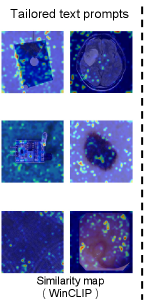

Anomaly detection (AD) has been widely applied in various applications, such as industrial defect inspection (bergmann2019mvtec; xie2023pushing; roth2022towards; huang2022registration; mou2022rgi; chen2022deep; bergmann2020uninformed; pang2021explainable; reiss2023mean; you2022unified; liznerski2020explainable; ding2022catching; 9940966; cao2023anomaly) and medical image analysis (pang2021explainable; qin2022medical; liu2023clip; ding2022catching; tian2021constrained; tian2023self; fernando2021deep). Existing AD approaches typically assume that training examples in a target application domain are available for learning the detection models (pang2021deep; ruff2021unifying). However, this assumption may not hold in various scenarios, such as i) when accessing training data violates data privacy policies (e.g., to protect the sensitive information of patients), or ii) when the target domain does not have relevant training data (e.g., inspecting defects in a manufacturing line of new products). Zero-shot anomaly detection (ZSAD) is an emerging task for AD in such scenarios, to which the aforementioned AD approaches are not viable, as it requires detection models to detect anomalies without any training sample in a target dataset. Since anomalies from different application scenarios typically have substantial variations in their visual appearance, foreground objects, and background features, e.g., defects on the surface of one product vs. that on the other products, lesions/tumors on different organs, or industrial defects vs. tumors/lesions in medical images, detection models with strong generalization ability w.r.t. such variations are needed for accurate ZSAD. Recently large pre-trained vision-language models (VLMs) (radford2021learning; kirillov2023segment) have demonstrated strong zero-shot recognition ability in various vision tasks, including anomaly detection (jeong2023winclip). Particularly, being pre-trained using millions/billions of image-text pairs, CLIP (radford2021learning) has been applied to empower various downstream tasks (zhou2022learning; rao2022denseclip; khattak2023maple; sain2023clip) with its strong generalization capability. WinCLIP (jeong2023winclip) is a seminal work in the ZSAD line, which designs a large number of artificial text prompts to exploit the CLIP’s generalizability for ZSAD. However, the VLMs such as CLIP are primarily trained to align with the class semantics of foreground objects rather than the abnormality/normality in the images, and as a result, their generalization in understanding the visual abnormality/normality is restricted, leading to weak ZSAD performance. Further, the current prompting approaches, using either manually defined text prompts (jeong2023winclip) or learnable prompts (sun2022dualcoop; zhou2022conditional), often result in prompt embeddings that opt for global features for effective object semantic alignment (zhong2022regionclip; wu2023aligning), failing to capture the abnormality that often manifests in fine-grained, local features, as shown in Fig. 1d and Fig. 1e. In this paper we introduce a novel approach, namely AnomalyCLIP, to adapt CLIP for accurate ZSAD across different domains. AnomalyCLIP aims to learn object-agnostic text prompts that capture generic normality and abnormality in an image regardless of its foreground objects. It first devises a simple yet universally-effective learnable prompt template for the two general classes – normality and abnormality – and then utilizes both image-level and pixel-level loss functions to learn the generic normality and abnormality globally and locally in our prompt embeddings using auxiliary data. This allows our model to focus on the abnormal image regions rather the object semantics, enabling remarkable zero-shot capability of recognizing the abnormality that has similar abnormal patterns to those in auxiliary data. As shown in Fig. 1a and Fig. 1b, the foreground object semantics can be completely different in the fine-tuning auxiliary data and target data, but the anomaly patterns remain similar, e.g., scratches on metal nuts and plates, the misplacement of transistors and PCB, tumors/lesions on various organ surfaces, etc. Text prompt embeddings in CLIP fail to generalize across different domains, as illustrated in Fig. 1c, but object-agnostic prompt embeddings learned by AnomalyCLIP can effectively generalize to recognize the abnormality across different domain images in Fig. 1f.

Figure 1: Comparison of ZSAD results on (b) test data using (c) original text prompts in CLIP (radford2021learning), (d) tailored text prompts for AD in WinCLIP (jeong2023winclip), (e) learnable text prompts for general vision tasks in CoOp (zhou2022conditional), and (f) object-agnostic text prompts in our AnomalyCLIP. (a) presents a set of auxiliary data we can use to learn the text prompts. The results are obtained by measuring the similarity between text prompt embeddings and image embeddings. The ground-truth anomaly regions are circled in red in (a) and (b). (c), (d), and (e) suffer from poor generalization across different domains, while our AnomalyCLIP in (f) can well generalize to anomalies in diverse types of objects from different domains.

Table 1 shows the ZSAD results of AnomalyCLIP with five competing methods over seven industrial defect datasets of very different foreground objects, background, and/or anomaly types. AnomalyCLIP achieves superior ZSAD performance across the datasets, substantially outperforming the other five methods in most datasets. The weak performance of CLIP and CLIP-AC can be attributed to CLIP’s original pre-training, which focuses on aligning object semantics rather than anomaly semantics. By using manually defined text prompts, WinCLIP and VAND achieve better results. Alternatively, CoOp adopts learnable prompts to learn the global anomaly semantics. However, those prompts focus on the global feature and ignore the fine-grained local anomaly semantics, leading to their poor performance on anomaly segmentation. To adapt CLIP to ZSAD, AnomalyCLIP learns object-agnostic text prompts to focus on learning the generic abnormality/normality using global and local context optimization, enabling the modeling of both global and local abnormality/normality. Our resulting prompts can also generalize to different datasets from various domains. To provide more intuitive results, we visualize the anomaly segmentation results of AnomalyCLIP, VAND, and WinCLIP across different datasets in Fig. 4. Compared to VAND and WinCLIP, AnomalyCLIP can perform much more accurate segmentation for the defects from different industrial inspection domains.

Generalization from defect datasets to diverse medical domain datasets

To evaluate the generalization ability of our model, we further examine the ZSAD performance of AnomalyCLIP on 10 medical image datasets of different organs across different imaging devices. Table 2 shows the results, where learning-based methods, including AnomalyCLIP, VAND and CoOp, are all tuned using MVTec AD data. It is remarkable that methods like AnomalyCLIP and VAND obtain promising ZSAD performance on various medical image datasets, even though they are tuned using a defect detection dataset. Among all these methods, AnomalyCLIP is the best performer due to its strong generalization brought by object-agnostic prompt learning. As illustrated in Fig. 4, AnomalyCLIP can accurately detect various types of anomalies in diverse medical images, such as skin cancer regions in photography images, colon polyps in endoscopy images, thyroid nodules in ultrasound images, and brain tumors in MRI images, having substantially better performance in locating the abnormal lesion/tumor regions than the other two methods WinCLIP and VAND. This again demonstrates the superior ZSAD performance of AnomalyCLIP in datasets of highly diverse object semantics from medical imaging domains.

Refer to caption

Figure 4: Segmentation visualization.